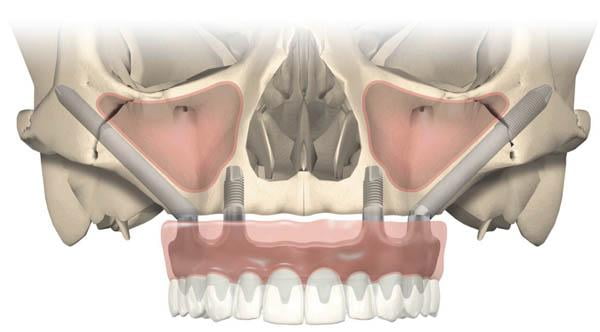

Zygomatic dental implants are a type of dental implant that is used when traditional dental implants cannot be placed due to inadequate bone density in the jaw. These implants are anchored in the zygomatic bone, which is located in the cheekbone area and provides a sturdy foundation for dental implants.

One of the benefits of zygomatic dental implants is that they can be used to replace a full arch of upper teeth, even if there is not enough bone in the jaw to support traditional dental implants. This can be a good option for people who have experienced significant bone loss due to periodontal disease or other dental issues.